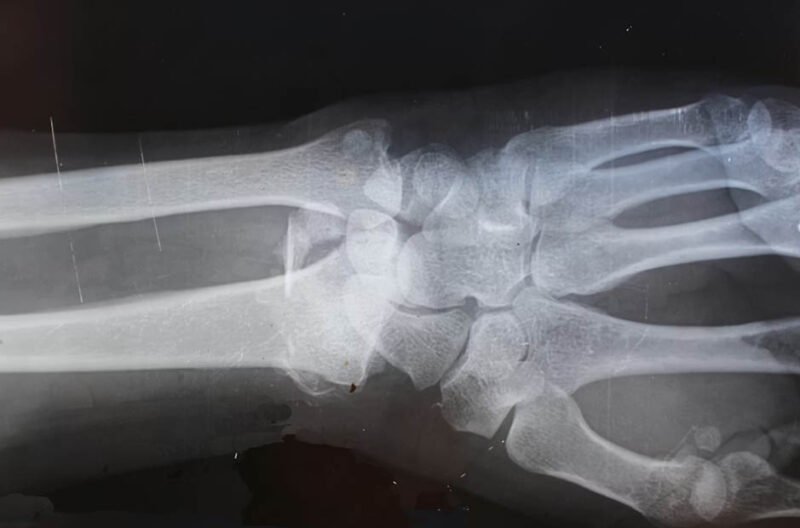

3. Visible Deformity or Abnormal Appearance

A fracture frequently alters the normal appearance of the affected body part. The injured area might appear bent or twisted in an unnatural way, or the limb might seem shorter than its opposite side. Even subtle changes in alignment can signal a break beneath the surface. The surrounding soft tissue often appears distorted as well, with unusual bumps or depressions where the bone structure has shifted. The skin over a fracture site might remain intact, but the underlying deformity often creates visible changes in the body’s natural contours. These changes become more apparent when comparing the injured area to the corresponding uninjured side. The affected limb might hang or rest in an unusual position, unable to maintain its normal alignment. In some cases, the deformity becomes more pronounced with movement or when bearing weight, as the broken bone segments shift in relation to each other.